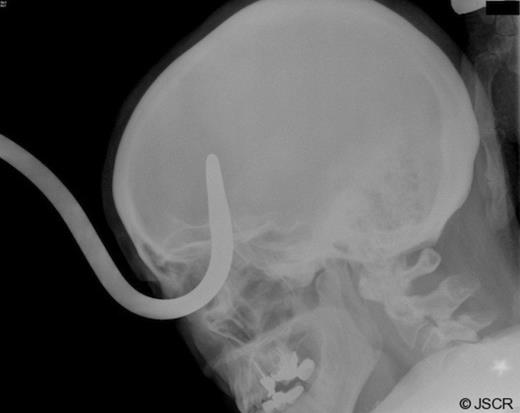

After obtaining a four view skull series x-ray (Figure 2), it became evident the object traveled through the right orbital fossa superiorly, with the tip projecting over the medial right frontal lobe anterior to the pituitary, fracturing the posterior supero-medial orbital wall. Secondary to the size of the object, and with the assistance of emergency medical services and the fire department, the patient was taken outside to the ambulance bay where a plasma saw was utilized to separate the hook from the stanchion post in preparation for removal (Figure 3).